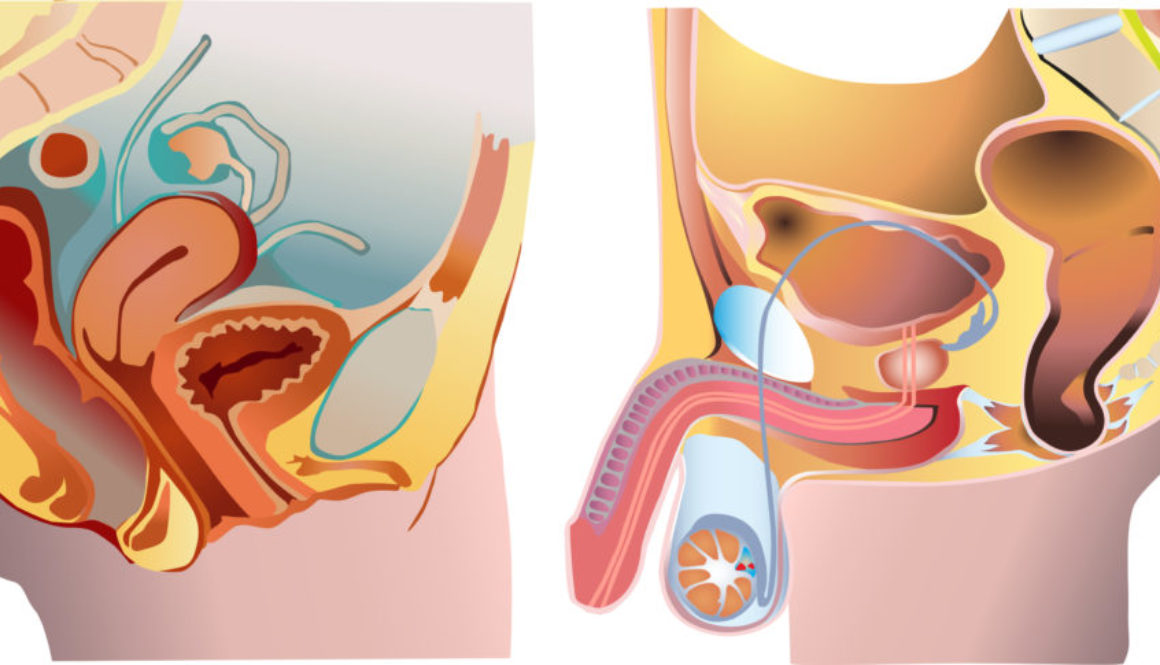

Desde los inicios de la reproducción asistida se ha buscado que las condiciones de los embriones en el laboratorio en cuanto a temperatura, oscuridad y niveles de Co2 y oxígeno reproduzcan las del útero materno.

Los sistemas de cultivo también han evolucionado y actualmente los embriones se mantienen en los incubadores en el interior de micro gotas. Pero, así como en su camino al útero los ovocitos viajan en condiciones de continuos

movimientos peristálticos y celulares e intercambio de metabolitos, en el laboratorio permanecen estáticos y como consecuencia, los productos tóxicos que liberan -radicales libres o amonio- se almacenan en el propio medio. Para evitarlo, algunas investigaciones recientes han aplicado vibraciones mecánicas a las placas de cultivo o bien han incorporado fluidos dinámicos a los medios de cultivo.